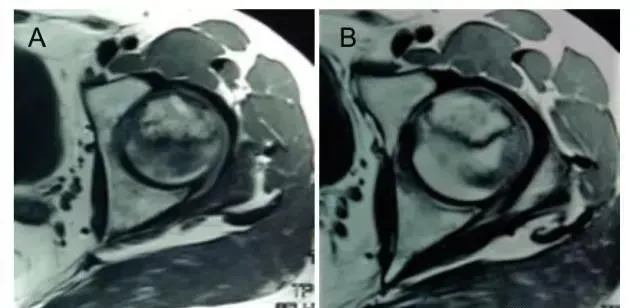

此外,MRI片上坏死面积较术前明显减小,治疗前坏死面积为(31.0±5.3)mm2,治疗后为(24.3±3.5)mm2,具有差别意义。

图A:MRI图像股骨头坏死;   图B:显示移植后股骨头坏死面积缩小。